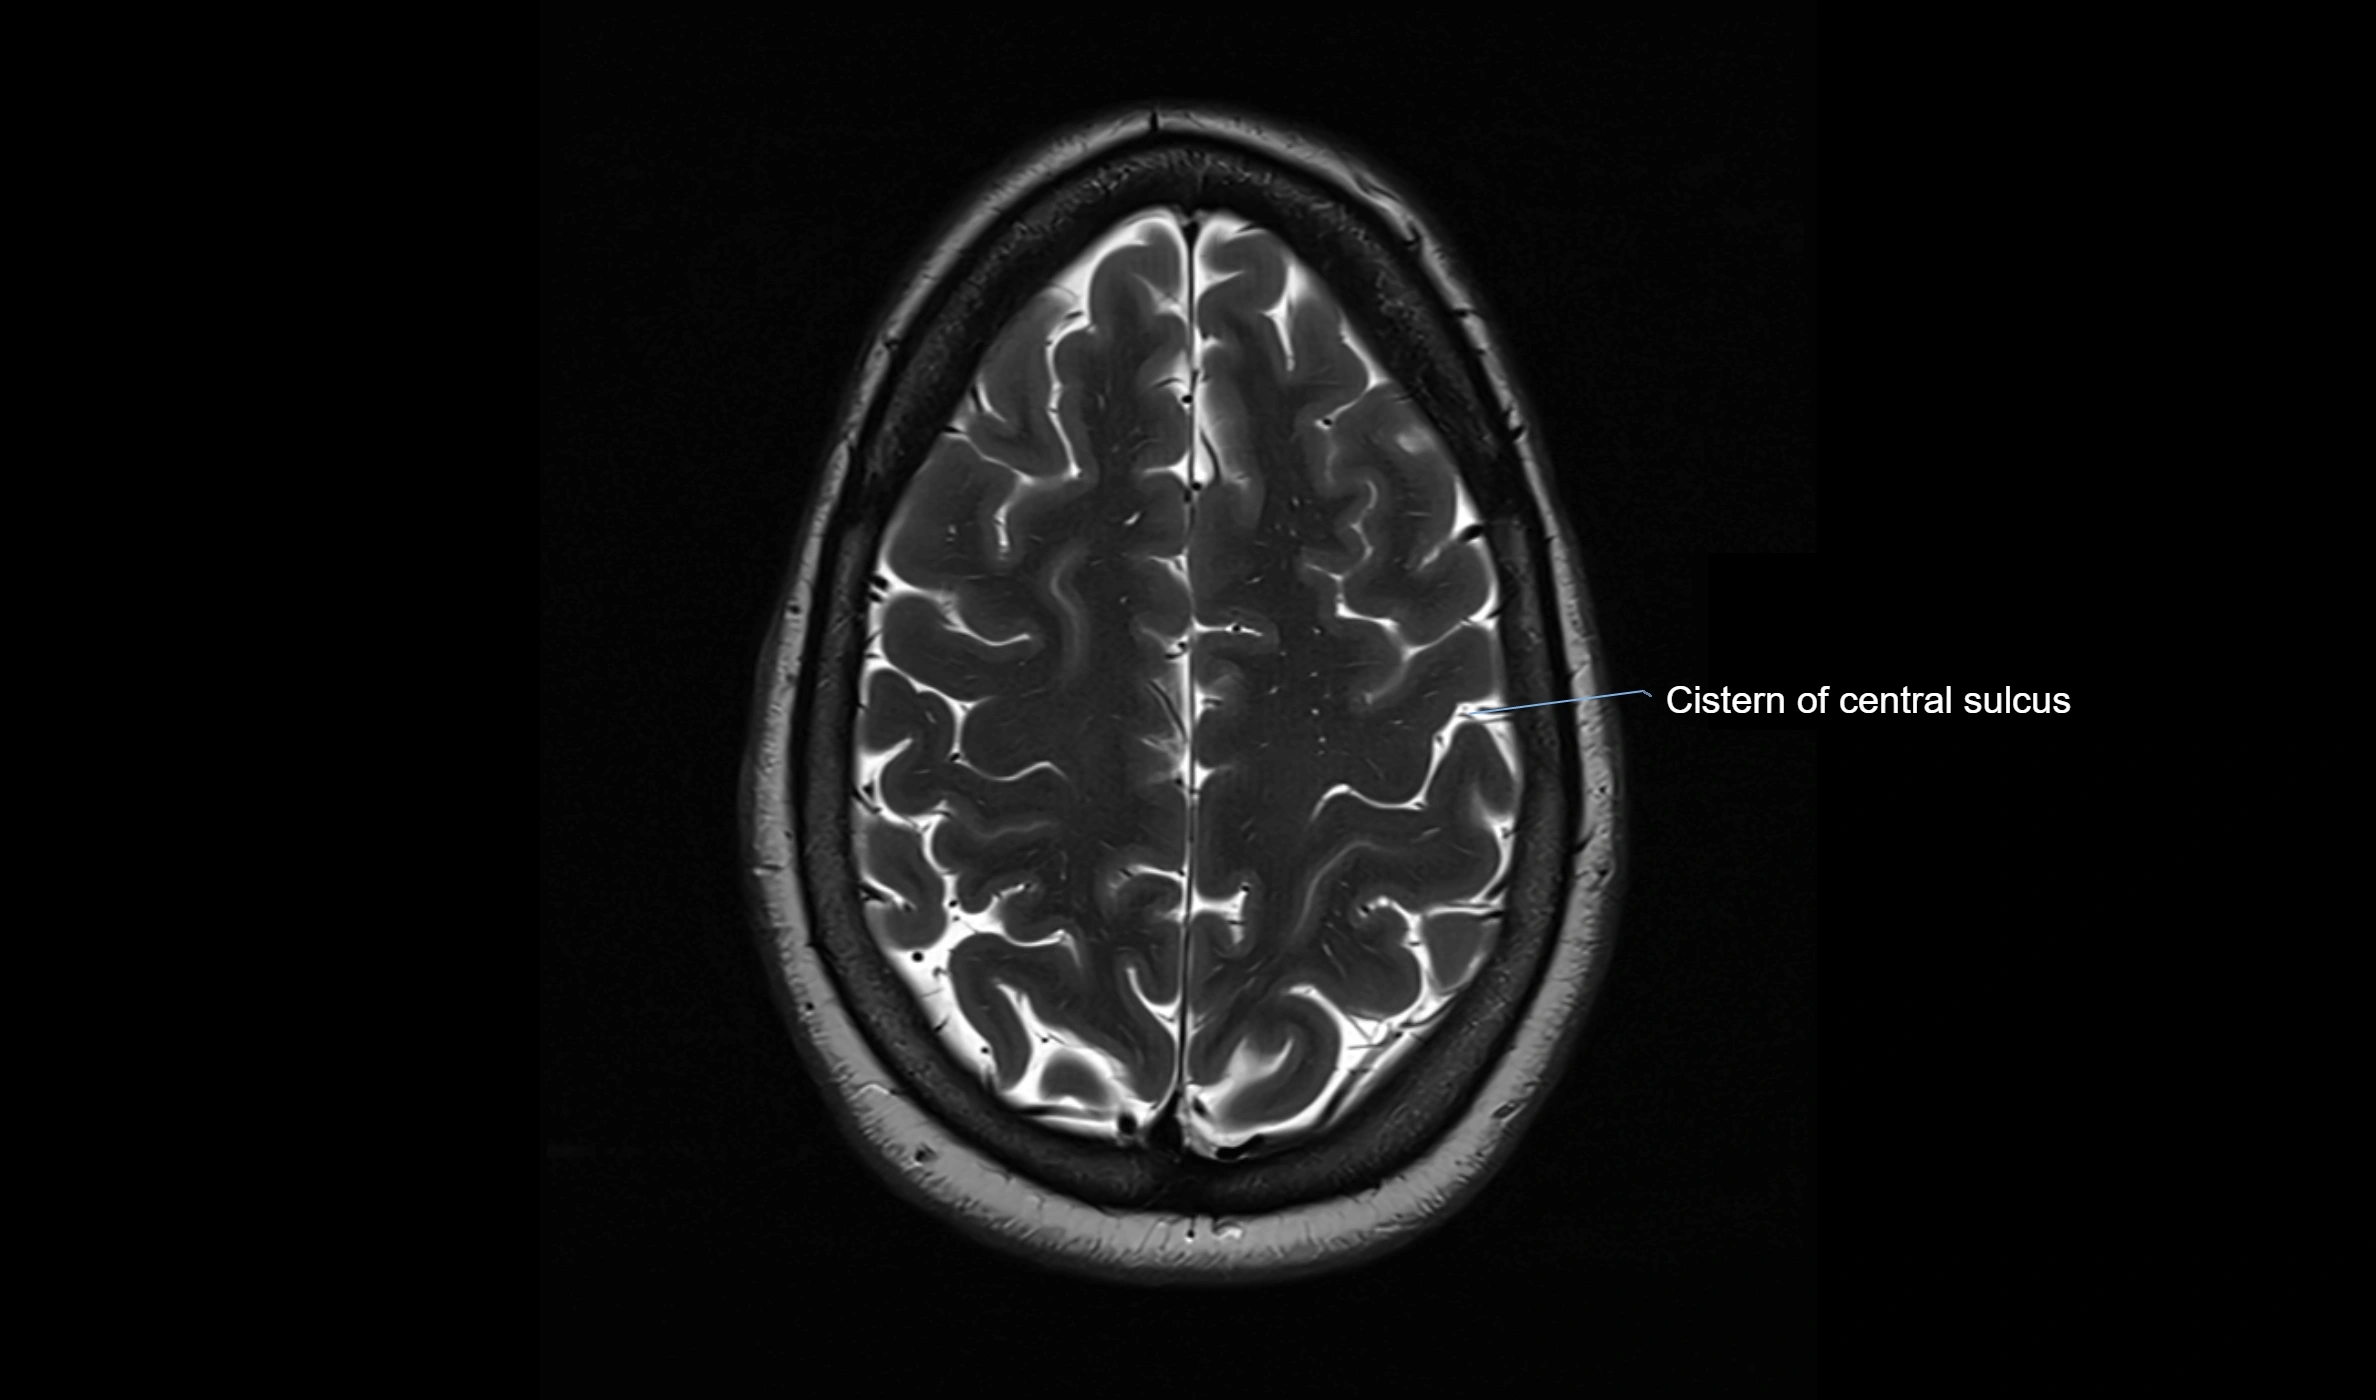

MRI images

image